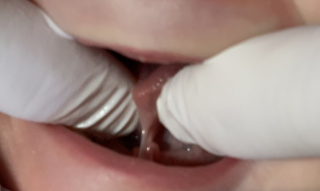

Rautenförmige Wunde

Bei der vollständigen Zungenbandtrennung entsteht am Zungengrund eine rautenförmige Wunde. Natürlicherweise würde der Zungengrund wieder «quer» zusammenwachsen. Ein solches reattachement würde erneut zu den Symptomen des kurzen Zungenbandes führen. Deshalb wird das postoperative Wundmanagement an die Lasertrennung angeschlossen.